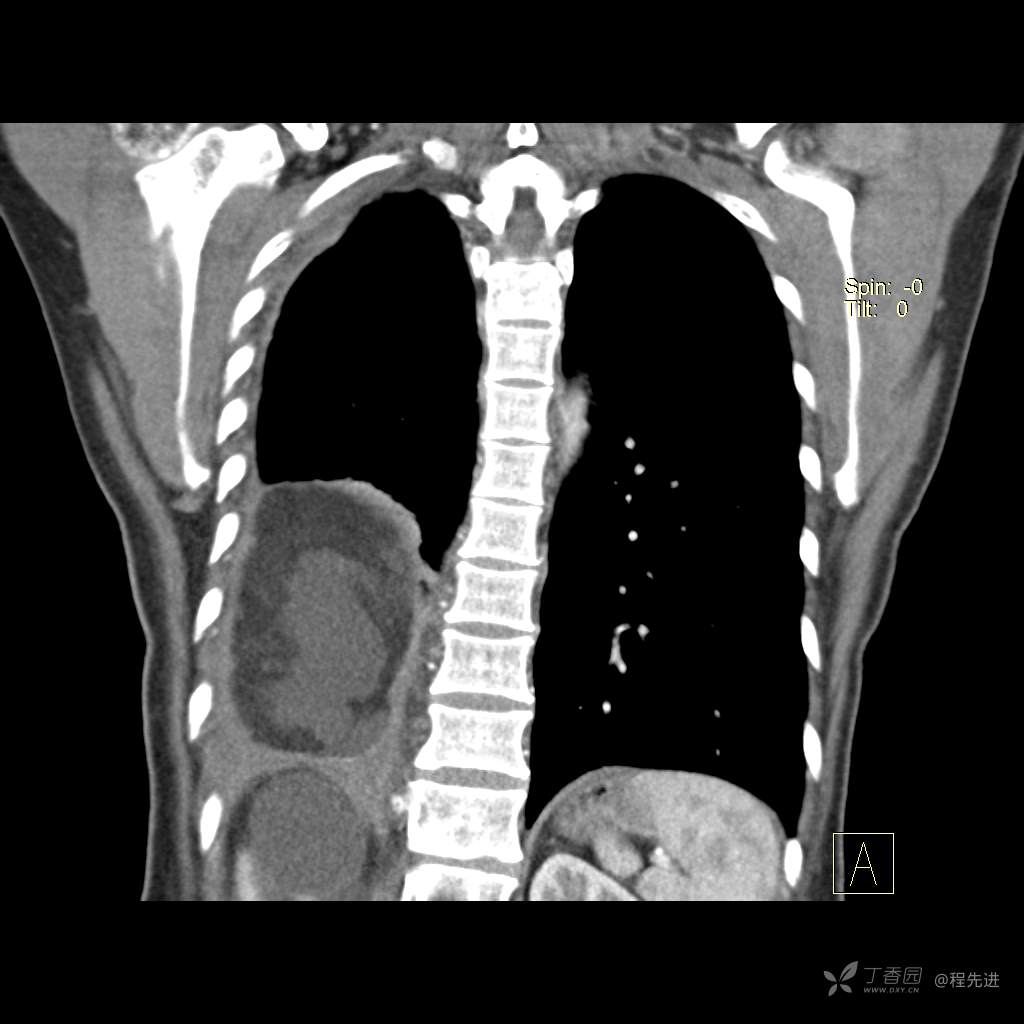

患者性别:女

患者年龄:51岁

简要病史:胸闷半年

肺淋巴管肌瘤病 (7)

乳糜胸 (8)